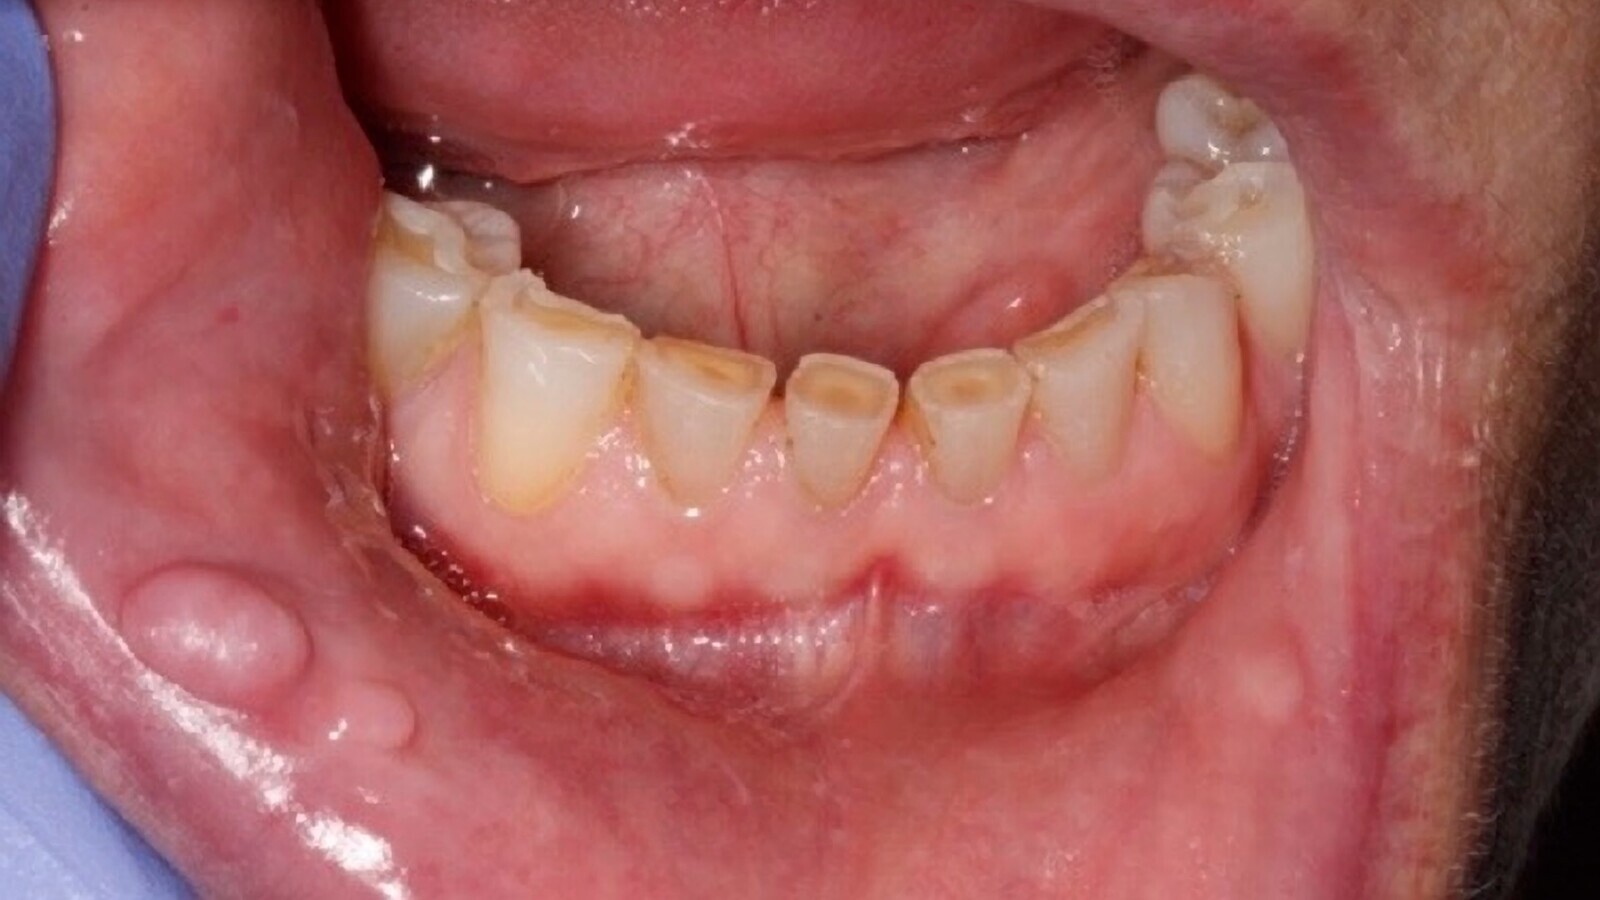

Tres lesiones frecuentes de la mucosa oral en pacientes mayores: úlcera traumática (a) que puede ser dolorosa y cuyas causas incluyen el uso de retenedores rotos; fibromas (b), que son lesiones delimitadas, localizadas en zonas de fricción e hiperplasia inflamatoria papilar (c).

Consiste en una pérdida de sustancia en que la lesión afecta a todo el espesor del epitelio. Suelen ser dolorosas y pueden dejar cicatriz. Existe una relación causa-efecto. Se deben eliminar los retenedores rotos, cambiar obturaciones antiguas con bordes cortantes, además de interrogar sobre hábitos alimentarios y parafuncionales (Figura 1).

Figura 1. Úlcera traumática que puede ser dolorosa y cuyas causas incluyen retenedores rotos, obturaciones antiguas con bordes cortantes y hábitos alimentarios del paciente.